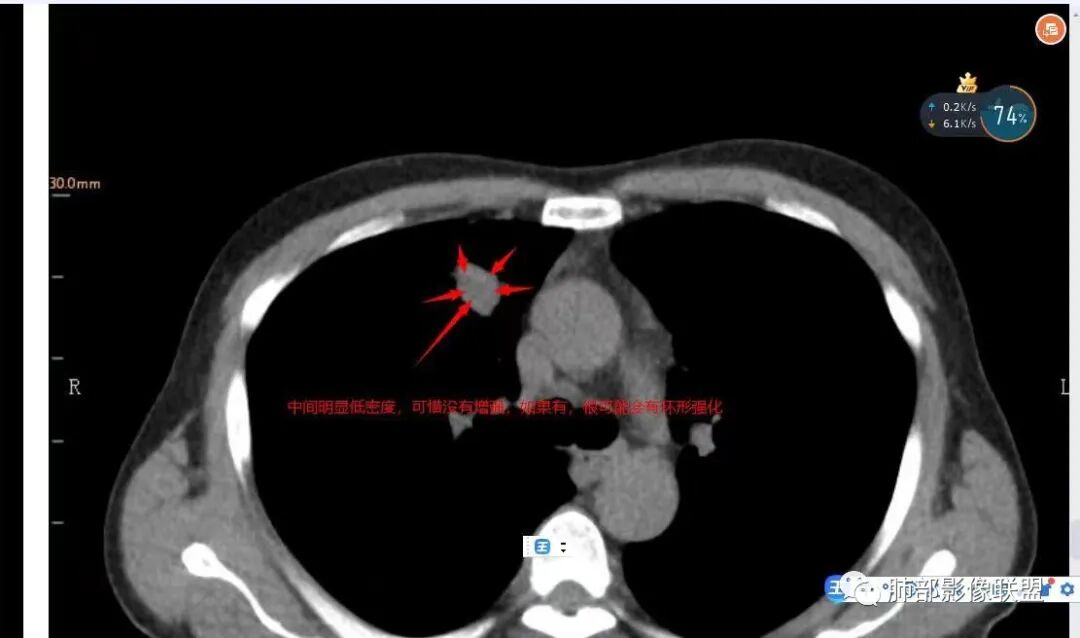

1.临床特点:52岁男性,体检发现肺结节。有吸烟史。非小细胞肺癌相关抗原与神经元烯醇化酶轻度升高。2.影像特点:右肺上叶前段可见不规则结节影,整体膨隆,可见浅分叶,周围局部可见边界清楚的磨玻璃影。可见血管集束征及脐凹征,临近叶间胸膜受牵拉凹陷,局部支气管到达病灶边缘后显示截断。3.病例小结:中老年吸烟男性,右肺上叶前段不规则结节,膨胀感较明显,收缩力强,支气管截断,加上边界清楚的磨玻璃影。符合浸润性腺癌表现。